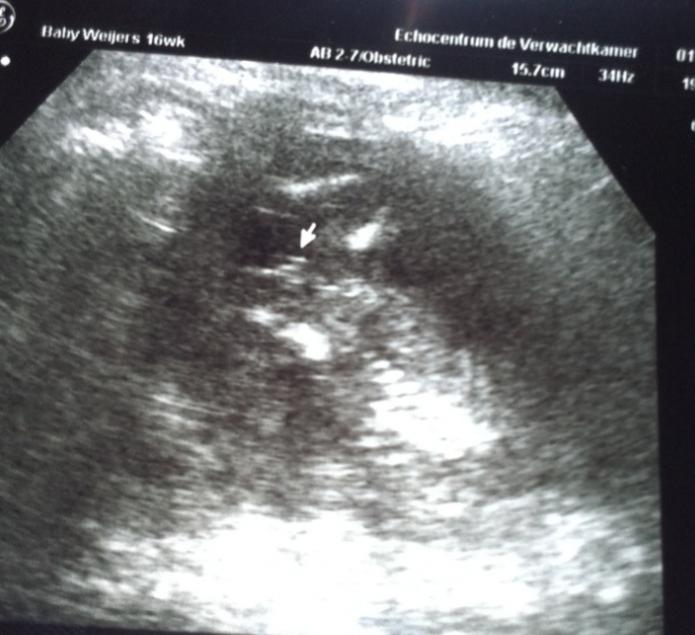

Girl ultrasound at 15 wk 6 days